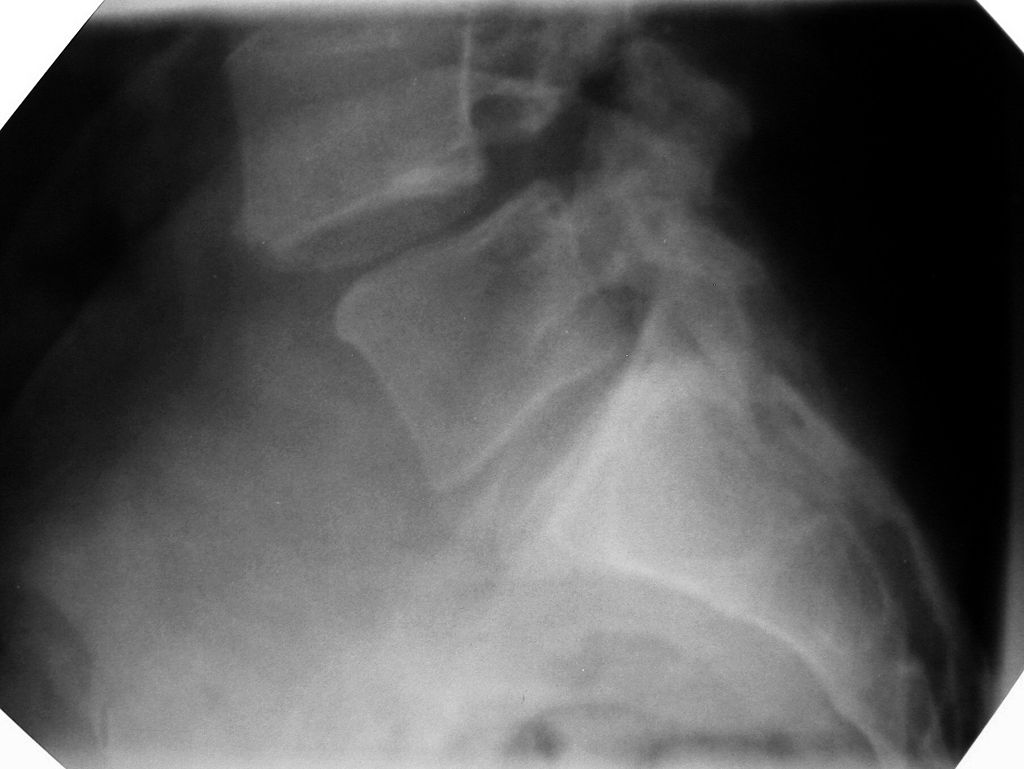

척추전방전위증의 엑스레이(x-ray) 촬영 이미지